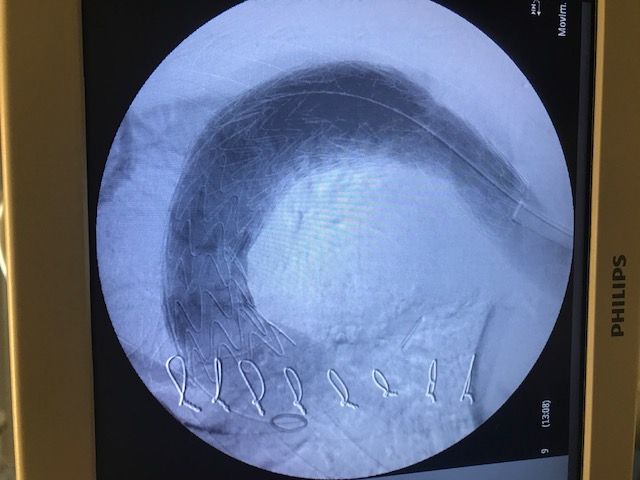

Cirugía de aorta ( aneurismas ), endoprótesis, cirugia abierta

- Cirugía endovascular

- Aneurisma aórtico